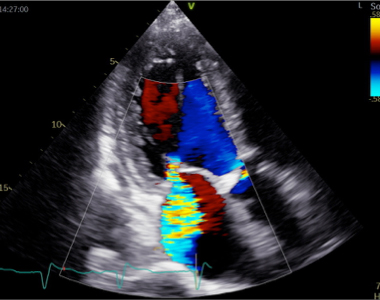

心エコー図検査は体に害のない、痛みを伴わない検査です。どの弁が障害されているのかを特定し、その動きや狭窄・逆流の程度を診断します。同時に、心臓の部屋の大きさや機能を診断しますが、これらは治療方針に直結します。体に負担のない検査なので、治療後に繰り返し検査をして、どの程度改善しているかを評価することもできます。さらに、手術が必要な方には、心臓血管外科医が手術を行う際に必要となる様々な情報を提供します。

血流に色をつけて表示する技術により、速い血流や遅い血流、逆流の有無やその程度がわかります。